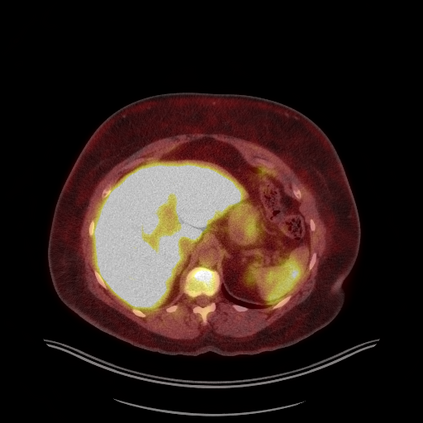

Medical images play a crucial role in assisting diagnosis, remote consultation, and academic research. However, during the transmission and sharing process, they face serious risks of copyright ownership and content tampering. Therefore, protecting medical images is of great importance. As an effective means of image copyright protection, zero-watermarking technology focuses on constructing watermarks without modifying the original carrier by extracting its stable features, which provides an ideal approach for protecting medical images. This paper aims to propose a fragile zero-watermarking model based on dual quaternion matrix decomposition, which utilizes the operational relationship between the standard part and the dual part of dual quaternions to correlate the original carrier image with the watermark image, and generates zero-watermarking information based on the characteristics of dual quaternion matrix decomposition, ultimately achieving copyright protection and content tampering detection for medical images.